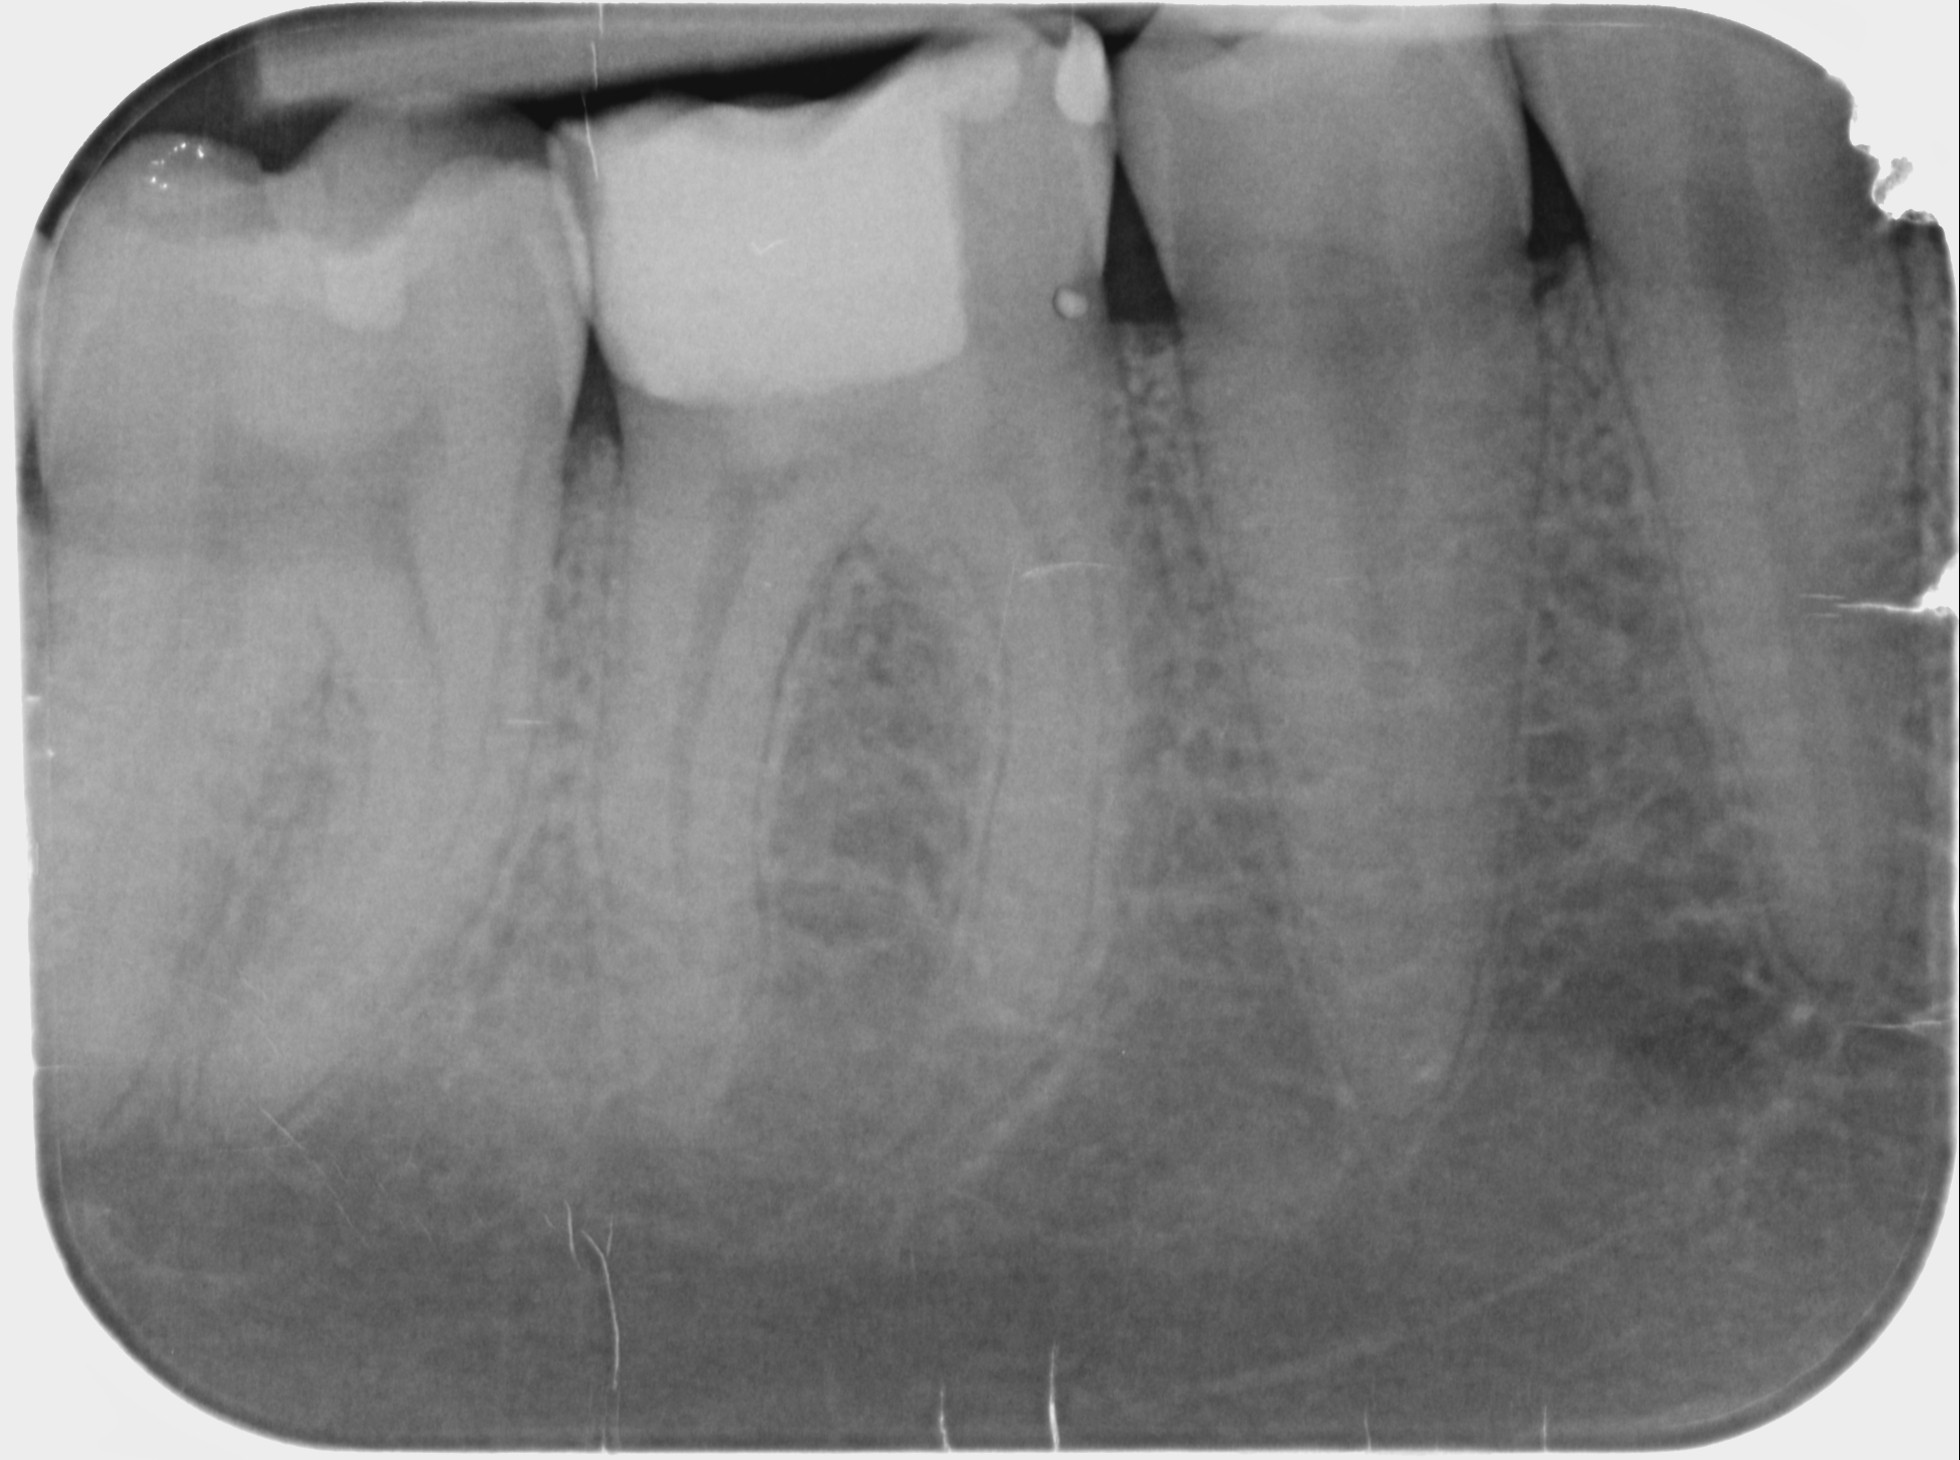

Knochenauflösungen an der Wurzelspitze (Röntgenbild)